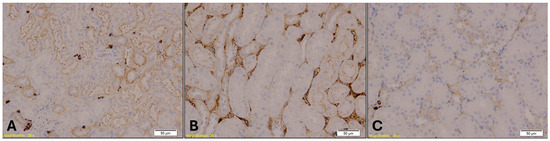

- E-cadherin (mouse monoclonal, 1:200)—Kidney: E-cadherin is a transmembrane protein involved in epithelial cell adhesion and polarity. Its expression is typically preserved in distal renal tubules but reduced in proximal segments. Loss or reduction in E-cadherin staining may reflect epithelial stress or ischemic injury, making it a useful marker for assessing hypothermia-induced renal damage.